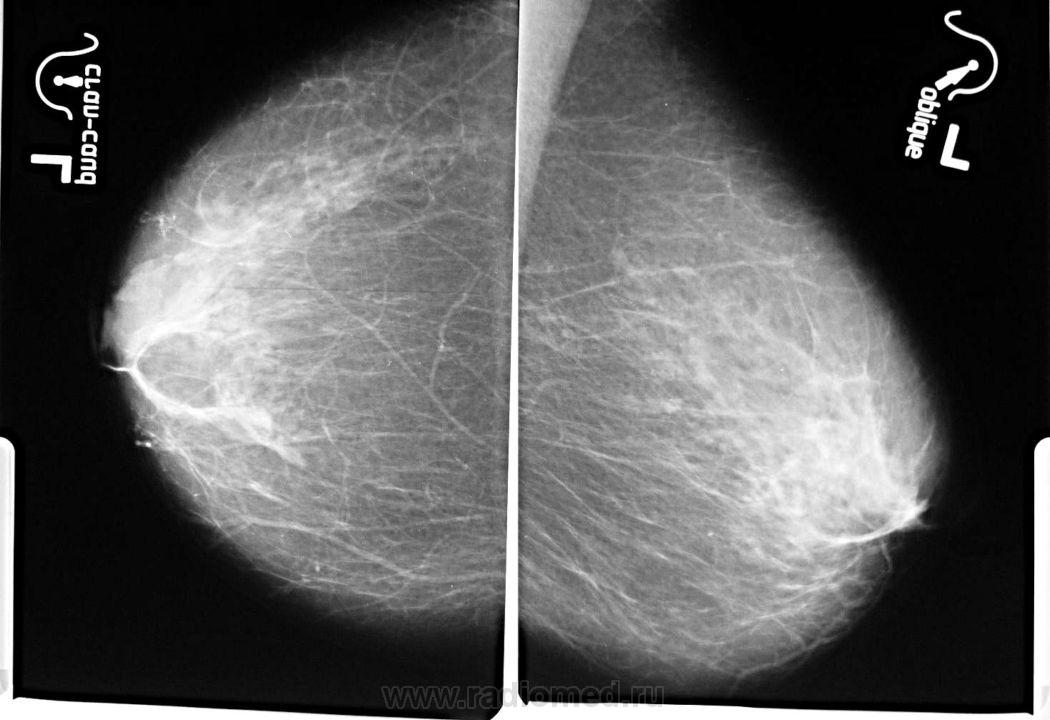

Ваше мнение о левой железе..?

образование жировой плотности - липома или жиросодержащая киста

Липома, с толстой фиброзной капсулой, должна пальпироваться. Для жиросодержащей кисты вроде как великовато.